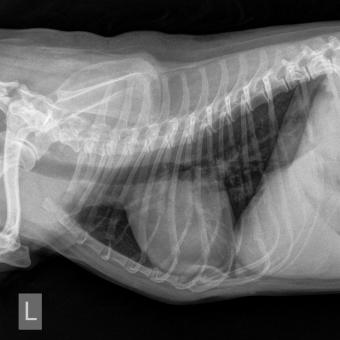

Eine Vergrösserung der Herz-Silhouette auf beiden Aufnahme-Ebenen des Brustkorbes – aber auch eine Verdichtung des Lungengewebes (Flüssigkeitsansammlung im Interstitium den Bronchien und Alveolen) sind ernste Zeichen und veranlassen entweder direkt einen Therapieversuch, oder führen zu den unten aufgeführten weiteren Untersuchungen.

Röntgenaufnahmen des Brustkorbes auf zwei Ebenen mit vergrössertem und abgerundetem Herzschatten und Verdichtung im Lungengewebe.

Thorax Röntgen

seitliches Thorax Röntgen mit vergrösserter Herz-Silhouette und verdichtetem Lungengewebe